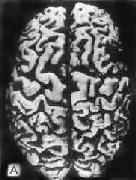

图16-32 初老期痴呆的脑 示脑明显萎缩(A),与正常脑(B)的对比 镜下,本病最主要的组织病变有:老年斑,神经原纤维缠结,颗粒空泡变性,Hirano小体等。 (1)老年斑:为细胞外结构,直径为20~150μm,最多见于内嗅区皮质、海马CA-1区,其次为额叶和顶叶皮质。银染色显示,斑块中心为一均匀的嗜银团,刚果红染色呈阳性反应,提示其中含淀粉样蛋白,其中含该蛋白的前体β/A-4蛋白及免疫球蛋白成分。中心周围有空晕环绕,外围有不规则嗜银颗粒或丝状物质。电镜下可见该斑块主要由多个异常扩张变性之轴索突触终末构成(图16-33)。